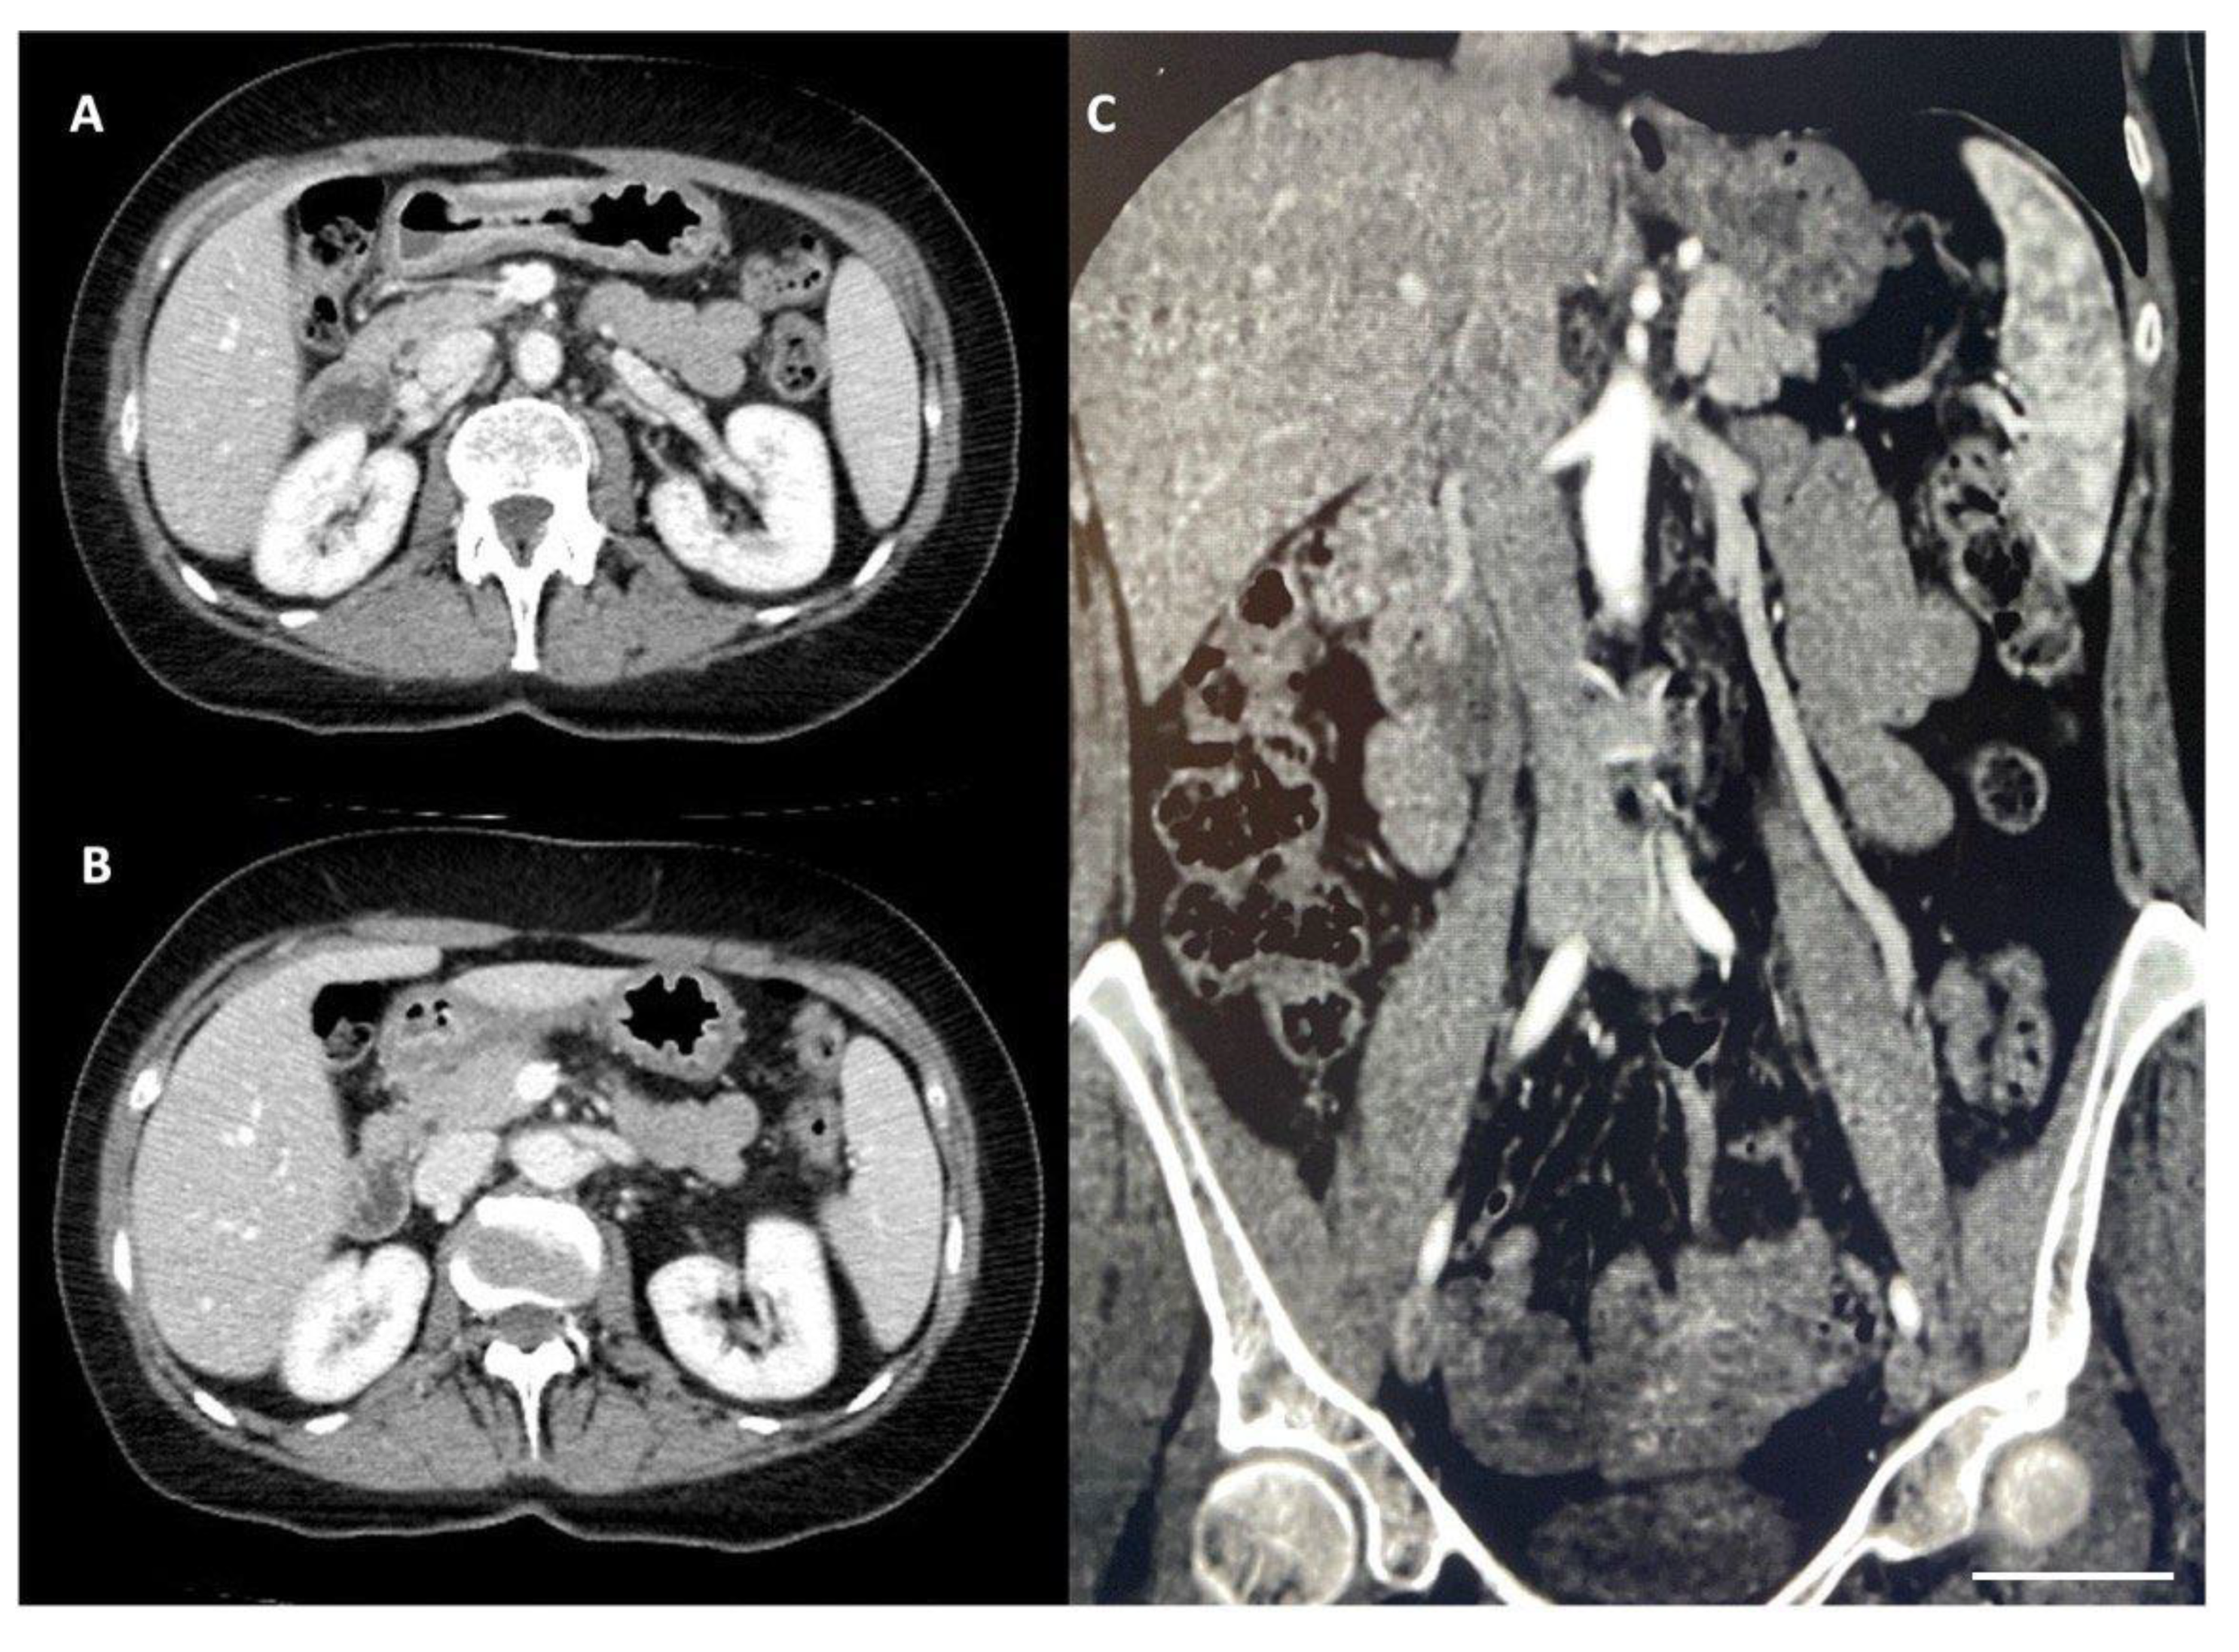

2. Case Report